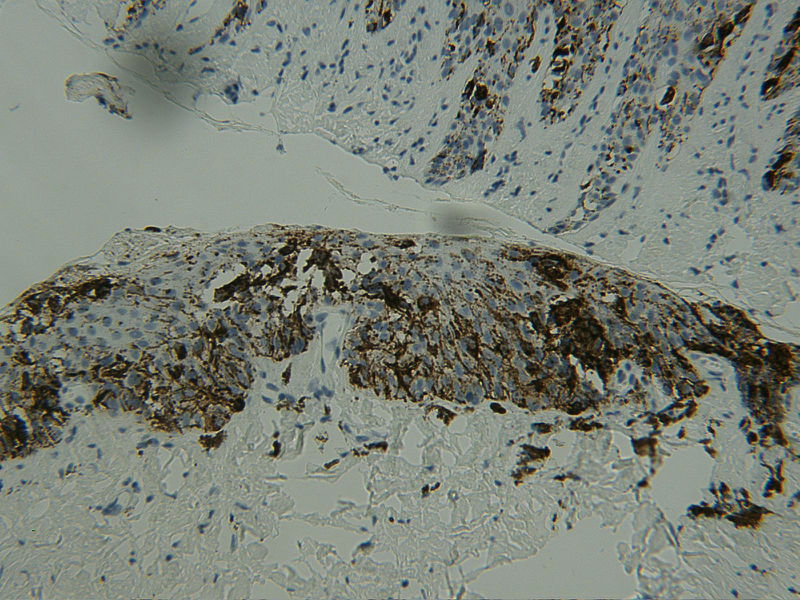

图3HMB45

女 68岁 右手拇指甲变黑及扩散2年,无自觉症状,有风湿性关节炎病史数年。